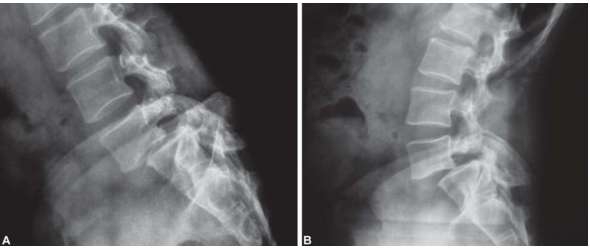

Bel Kayması

Omurga, omur denilen birbirine bağlı kemiklerden oluşur. Üstteki omur alttaki omur üzerinden öne doğru kayabilir. Bu duruma “bel kayması” ya da “spondilolistezis” denir. Kaymaya bağlı olarak omur etrafındaki sinirleri ve dokular zedelenebilir.

Bel kayması 4 derecedir